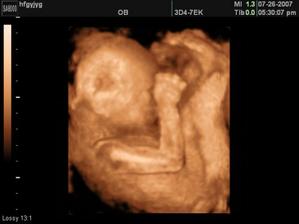

Míša kulička